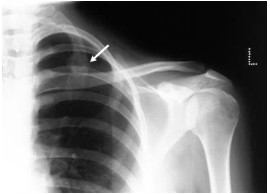

Bones of the human skeleton are divided into two main groups including axial skeleton and perpendicular skeleton. The bones of the appendicular skeleton creates the remaining skeleton. These are called appendicular because they are attachments of the axial skeleton. The appendicular skeleton comprises of the bones of the shoulder girdle, upper limbs, pelvic girdle and the lower limbs. Old-styled appendicular skeleton X-rays can help your doctor classify any damage from a shocking fall or mishap observe the development of a disease or trail the effects of assured treatment methods. Skeletal mobile X-rays are often done on an emergency basis after a suffering, such as a fall or misfortune. The physician will order an X-ray in any area that is causing immense pain in order to govern whether you have one or more broken bones. The physician may order a skeletal mobile X-ray if you display any marks or symptoms of circumstances that affect the bones, such as pain or swelling. These involve: arthritis, bone cancer, cancer that has spread to the bone, fractures, infections, osteoporosis and dental conditions. Contingent to the part under evaluation, the patient has to wear loose, contented clothing so that it is tranquil to move around. The patient is asked to take off any jewelry, spectacles, earsplitting or other metal items from your body before the mobile X-ray. The patient should inform the doctor if he/she have any metal grafts from prior surgeries. These may include a heart valve or pacemaker. In some occurrences the doctor may have selected to order a mobile X-ray because the patient have metal entrenched in the body. Different scans including MRI, can be dangerous for people with metal grafts.[Ske05]